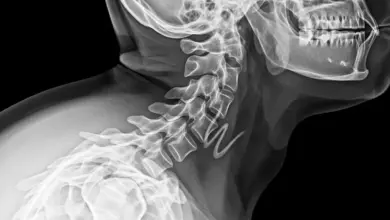

Síndrome de Klippel-Feil: sintomas, causas e tratamento

A síndrome de Klippel-Feil é uma condição congênita caracterizada pela fusão de duas ou mais vértebras cervicais, o que pode…

Mielopatia cervical: como reconhecer e tratar

A mielopatia cervical ocorre quando a medula espinhal é comprimida no pescoço, gerando perda de função neurológica, onde identificar cedo…

Disco osteofitários C4 C5 C6 C7: sintomas e tratamentos

Se o seu laudo cita disco osteofitários C4 C5 C6 C7, significa que houve desgaste do disco com formação de…